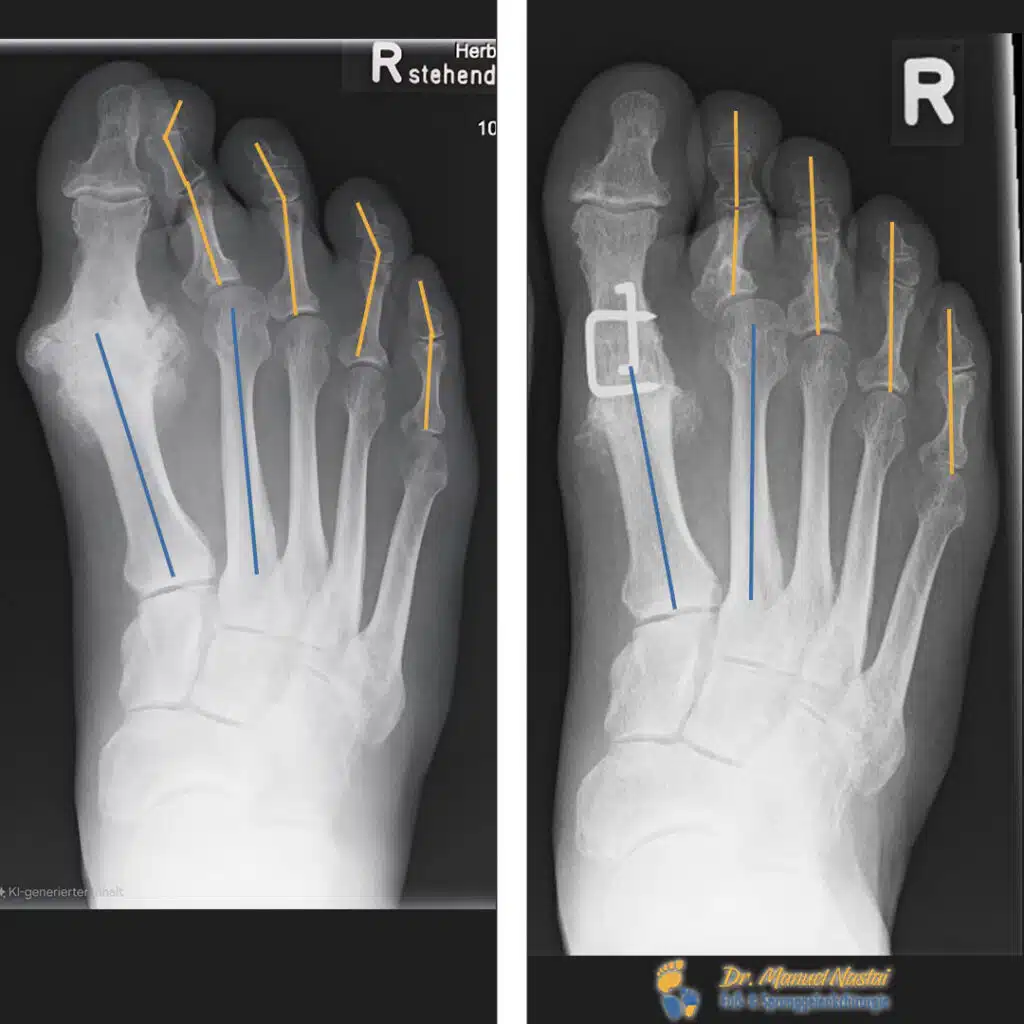

Prominente, druckdolente Vergrößerung des MTP‑I mit osteophytären Ausziehungen, endgradige Steife mit aufgehobener Dorsalextension. Sekundär vermehrte Hornhaut lateral; Kleinzehen (siehe in Blau die Fehlstellung und den Großzeh in Orange) zeigen eine mediale Abweichung mit zeitweisem Überkreuzen.

Bildgebung Befund (DP und seitlich, unter Belastung):

MTP-I: Ausgeprägte, überwiegend hypertrophe Arthrose. Der Gelenkspalt ist weitgehend aufgehoben, subchondrale Sklerosen an Metatarsalköpfchen und Grundphalanx, randständige osteophytäre Anbauten dorsal und medial; Metatarsalköpfchen verbreitert. Keine Frakturzeichen.

Strahlen II–V: Zeichen einer Zehenfehlstellung mit Tendenz zu Hammer-/Krallenzehen, jedoch ohne eindeutige luxatorische Fehlstellung der MTP-Gelenke. Weichteile unauffällig.

Bild eines fortgeschrittenen Hallux rigidus (MTP-I-Arthrose, KL 3–4) rechts mit nahezu aufgehobenem Gelenkspalt, subchondraler Sklerose und dorsomedialen Osteophyten.

Operation

Entscheidung zur Arthrodese des MTP‑I als Goldstandard bei endgradiger Arthrose. Osteophyten wurden entfernt; die Gelenkflächen in Cup‑and‑Cone‑Technik vorbereitet und das Gelenk in funktioneller Stellung (leichte Dorsalextension und Valgus) kompressionsstabil fusioniert. Fixation mittels zweier Kompressionsklammern. Hautverschluss mit Klammerpflastern, sodass keine Fadenentfernung notwendig war. Zusätzlich wurden konfliktierende Kleinzehen minimalinvasiv gelöst, parallel gestellt und für sechs Wochen getapet.

Unmittelbar postoperativ geringe Schwellung und Blutung; sichtbare Achskorrektur. Nach drei Monaten durchgehende knöcherne Fusion in korrekter Stellung, regelrechte Implantatlage; klinisch schmerzfrei, regelrechtes Abrollen über den Ballen, beschwerdefreies Tragen von Konfektionsschuhen. Zehen liegen nebeneinander ohne Überkreuzen; die zuvor laterale Hornhautbildung rückläufig.